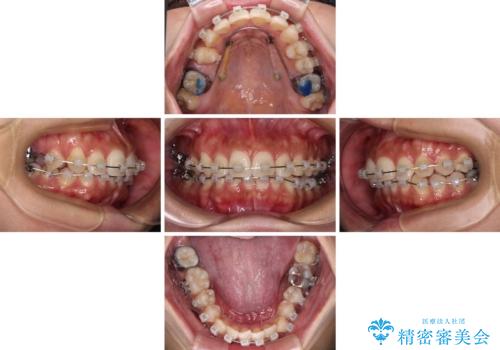

目立つ八重歯を改善 ワイヤー装置での抜歯矯正

- 目立つ八重歯を気にして来院された患者様です。

上顎小臼歯を抜歯するかどうか悩みましたが、八重歯の後方に失活歯があること、治療前に上顎正中が概ね人中に合っていることから、右上第二小臼歯を抜歯することとしました。

片側での抜歯であると、正中が抜歯した方向にずれていくため、左上の奥歯を遠心移動させる目的でアンカースクリューと補助装置を併用した上で、ワイヤー装置にて矯正治療を行うこととしました。